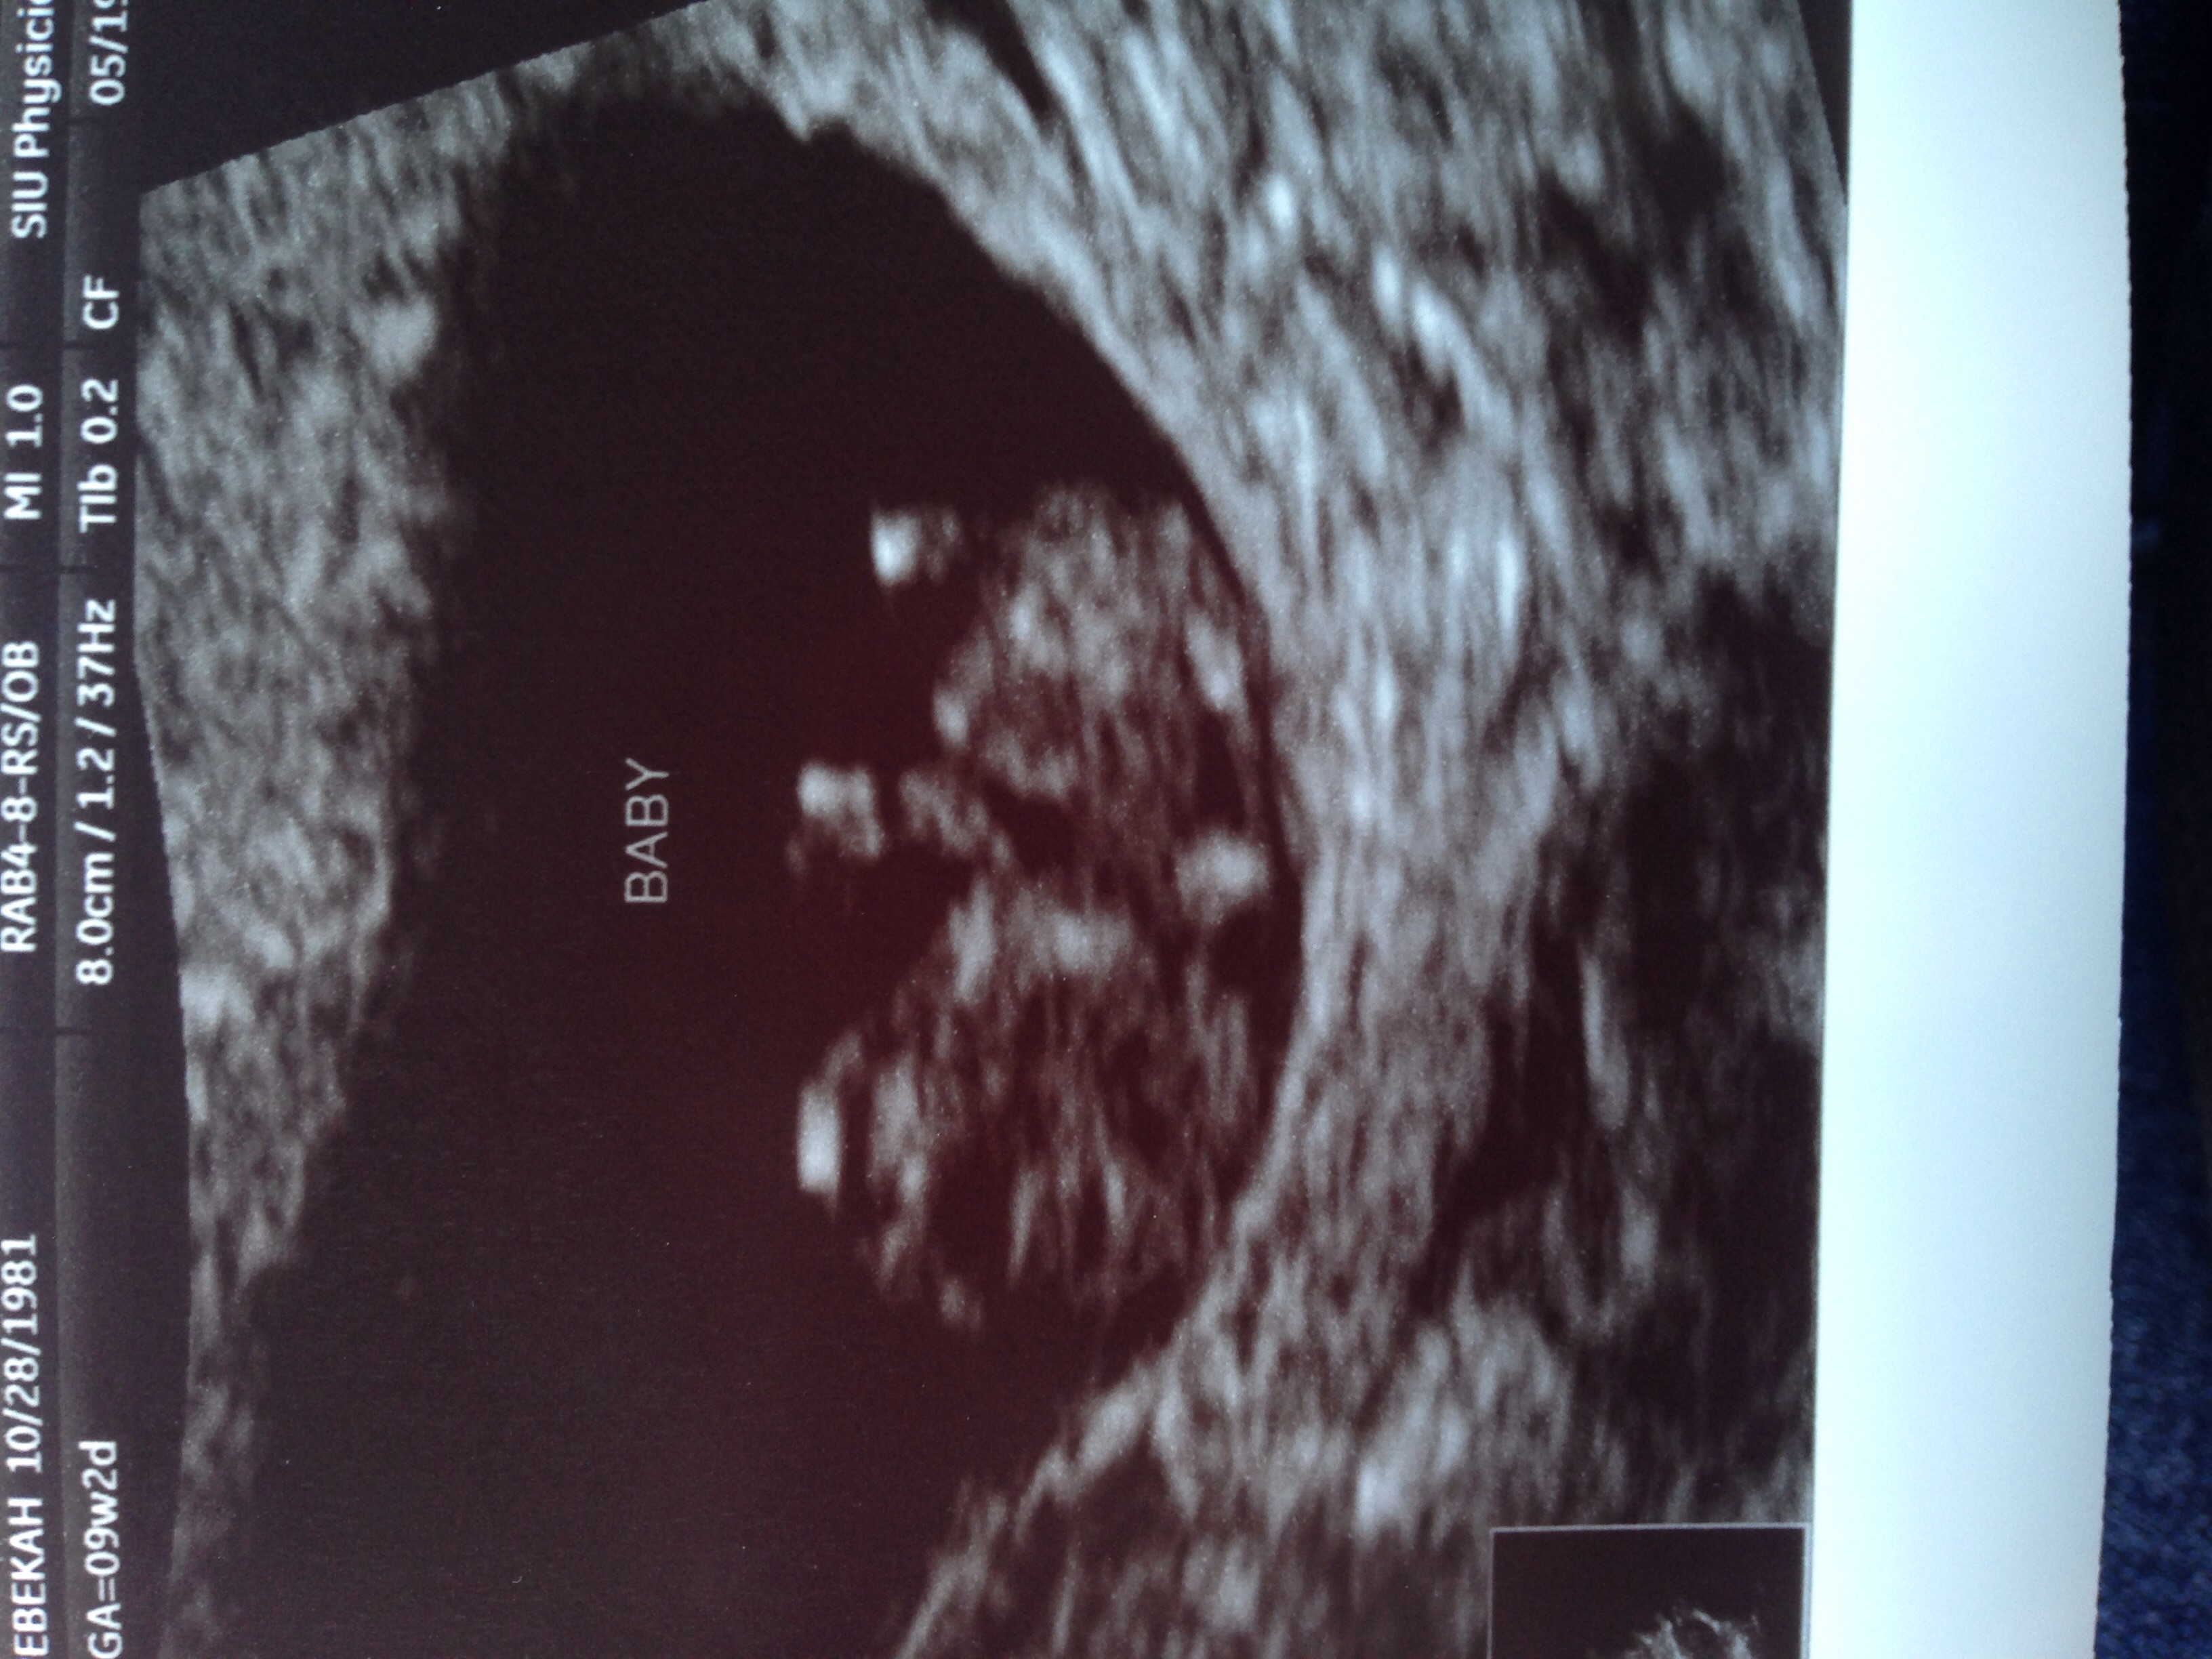

U/S is somewhat hard to see but head on left and arm bud sticking up, waving hi :-h Hi buddy!

Edit: oops, sideways pic confusion